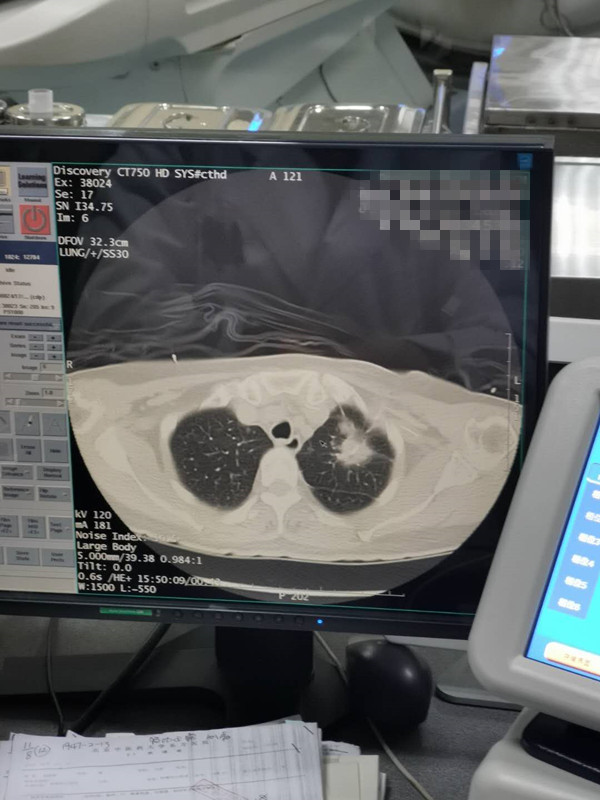

66岁肺部氩氦刀冷冻消融

发布人:美国氩氦刀技术官方网站    发布时间:2020/8/12 16:28:51